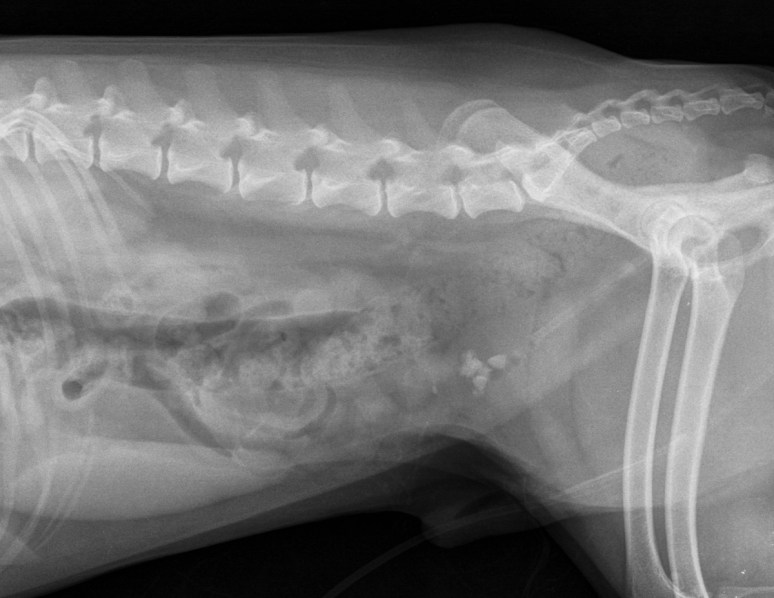

Voici deux images obtenues successivement, employant un système de cassettes et lecteur CR-30 de Agfa. Or, l’image du haut est de moins bonne qualité que celle du bas. Pourquoi selon vous ?